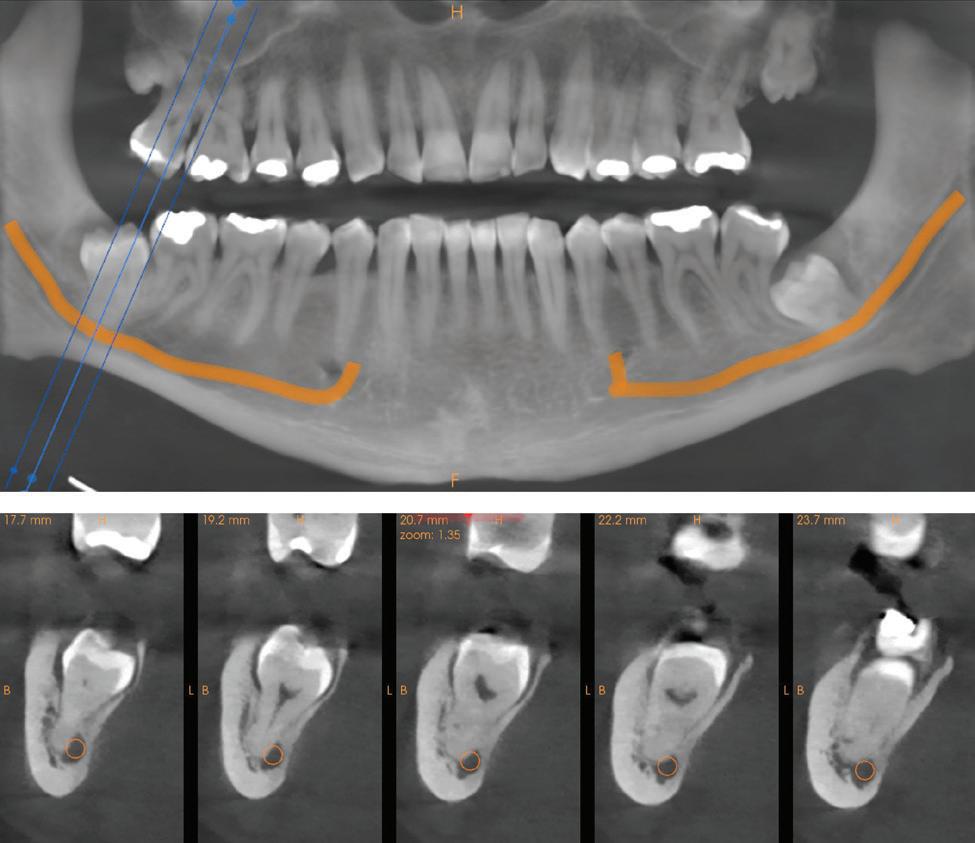

Figure 1: Radiographic Image of implants do not demonstrate bone loss due to the bisecting angle of the radiograph taken.

Figure 2: Radiographic image in a paralleling technique of implants dem onstrate moderate peri-implantitis with bone loss that will necessitate treatment.